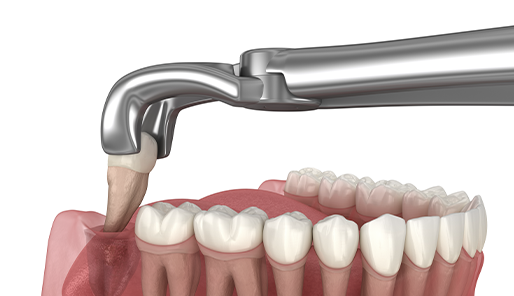

다 똑같은 임플란트가 아닙니다!

시술자의 숙련도에 따라 시술의 완성도가 달라지는

임플란트 치료는

환자의 상태를 정밀히 검진 후

그에 따른 맞춤 임플란트 치료를 받으셔야 합니다.

검증된 정품 임플란트 사용

대표원장 직접진료

통증 최소화

디지털 3D CAD/CAM 기술을 바탕으로

환자의 치아와 잇몸 모양에 맞춘 임플란트 보철물을 제작합니다.